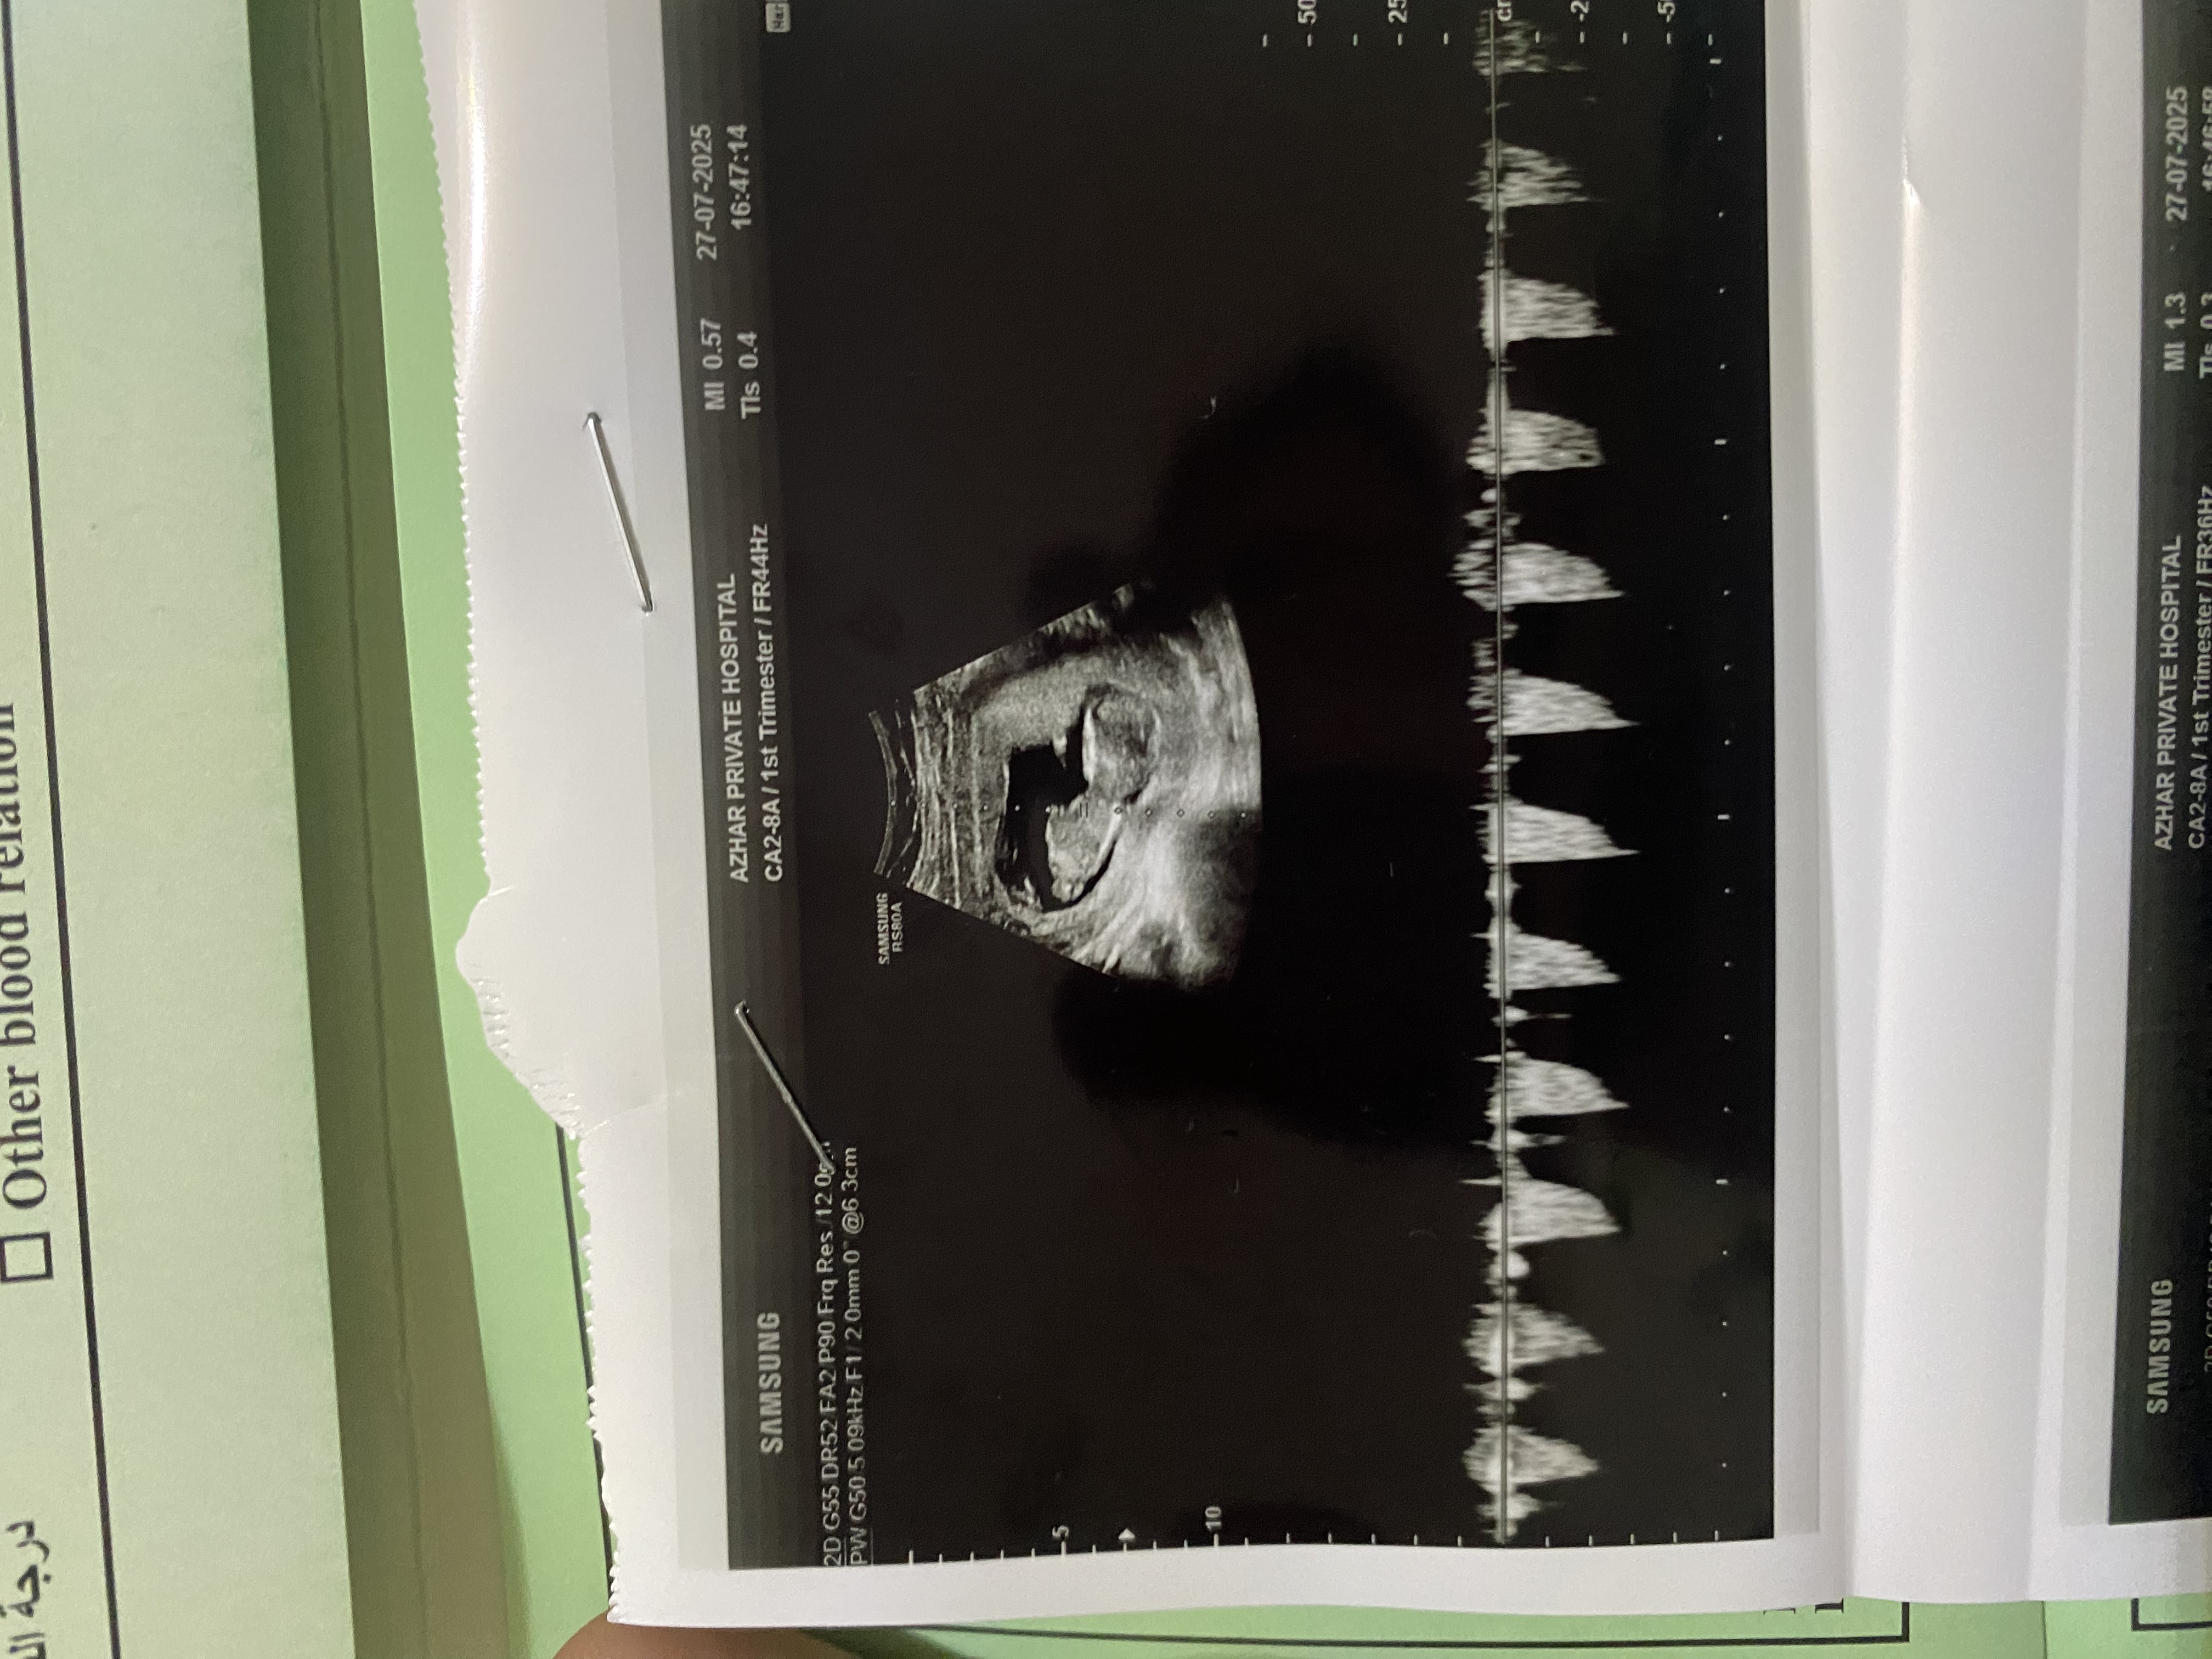

نه متاسفانه فقط همینو دارم دکتر احتمال دختر داده گفت چیزی معلوم نیس🥹

ببین تو این عکس تقریبا پشتش مشخصه

از نیمرخ اگه انتهای ستون فقرات یا همون لگن  تیز باشه پسره

اگه گرد باشه دختره